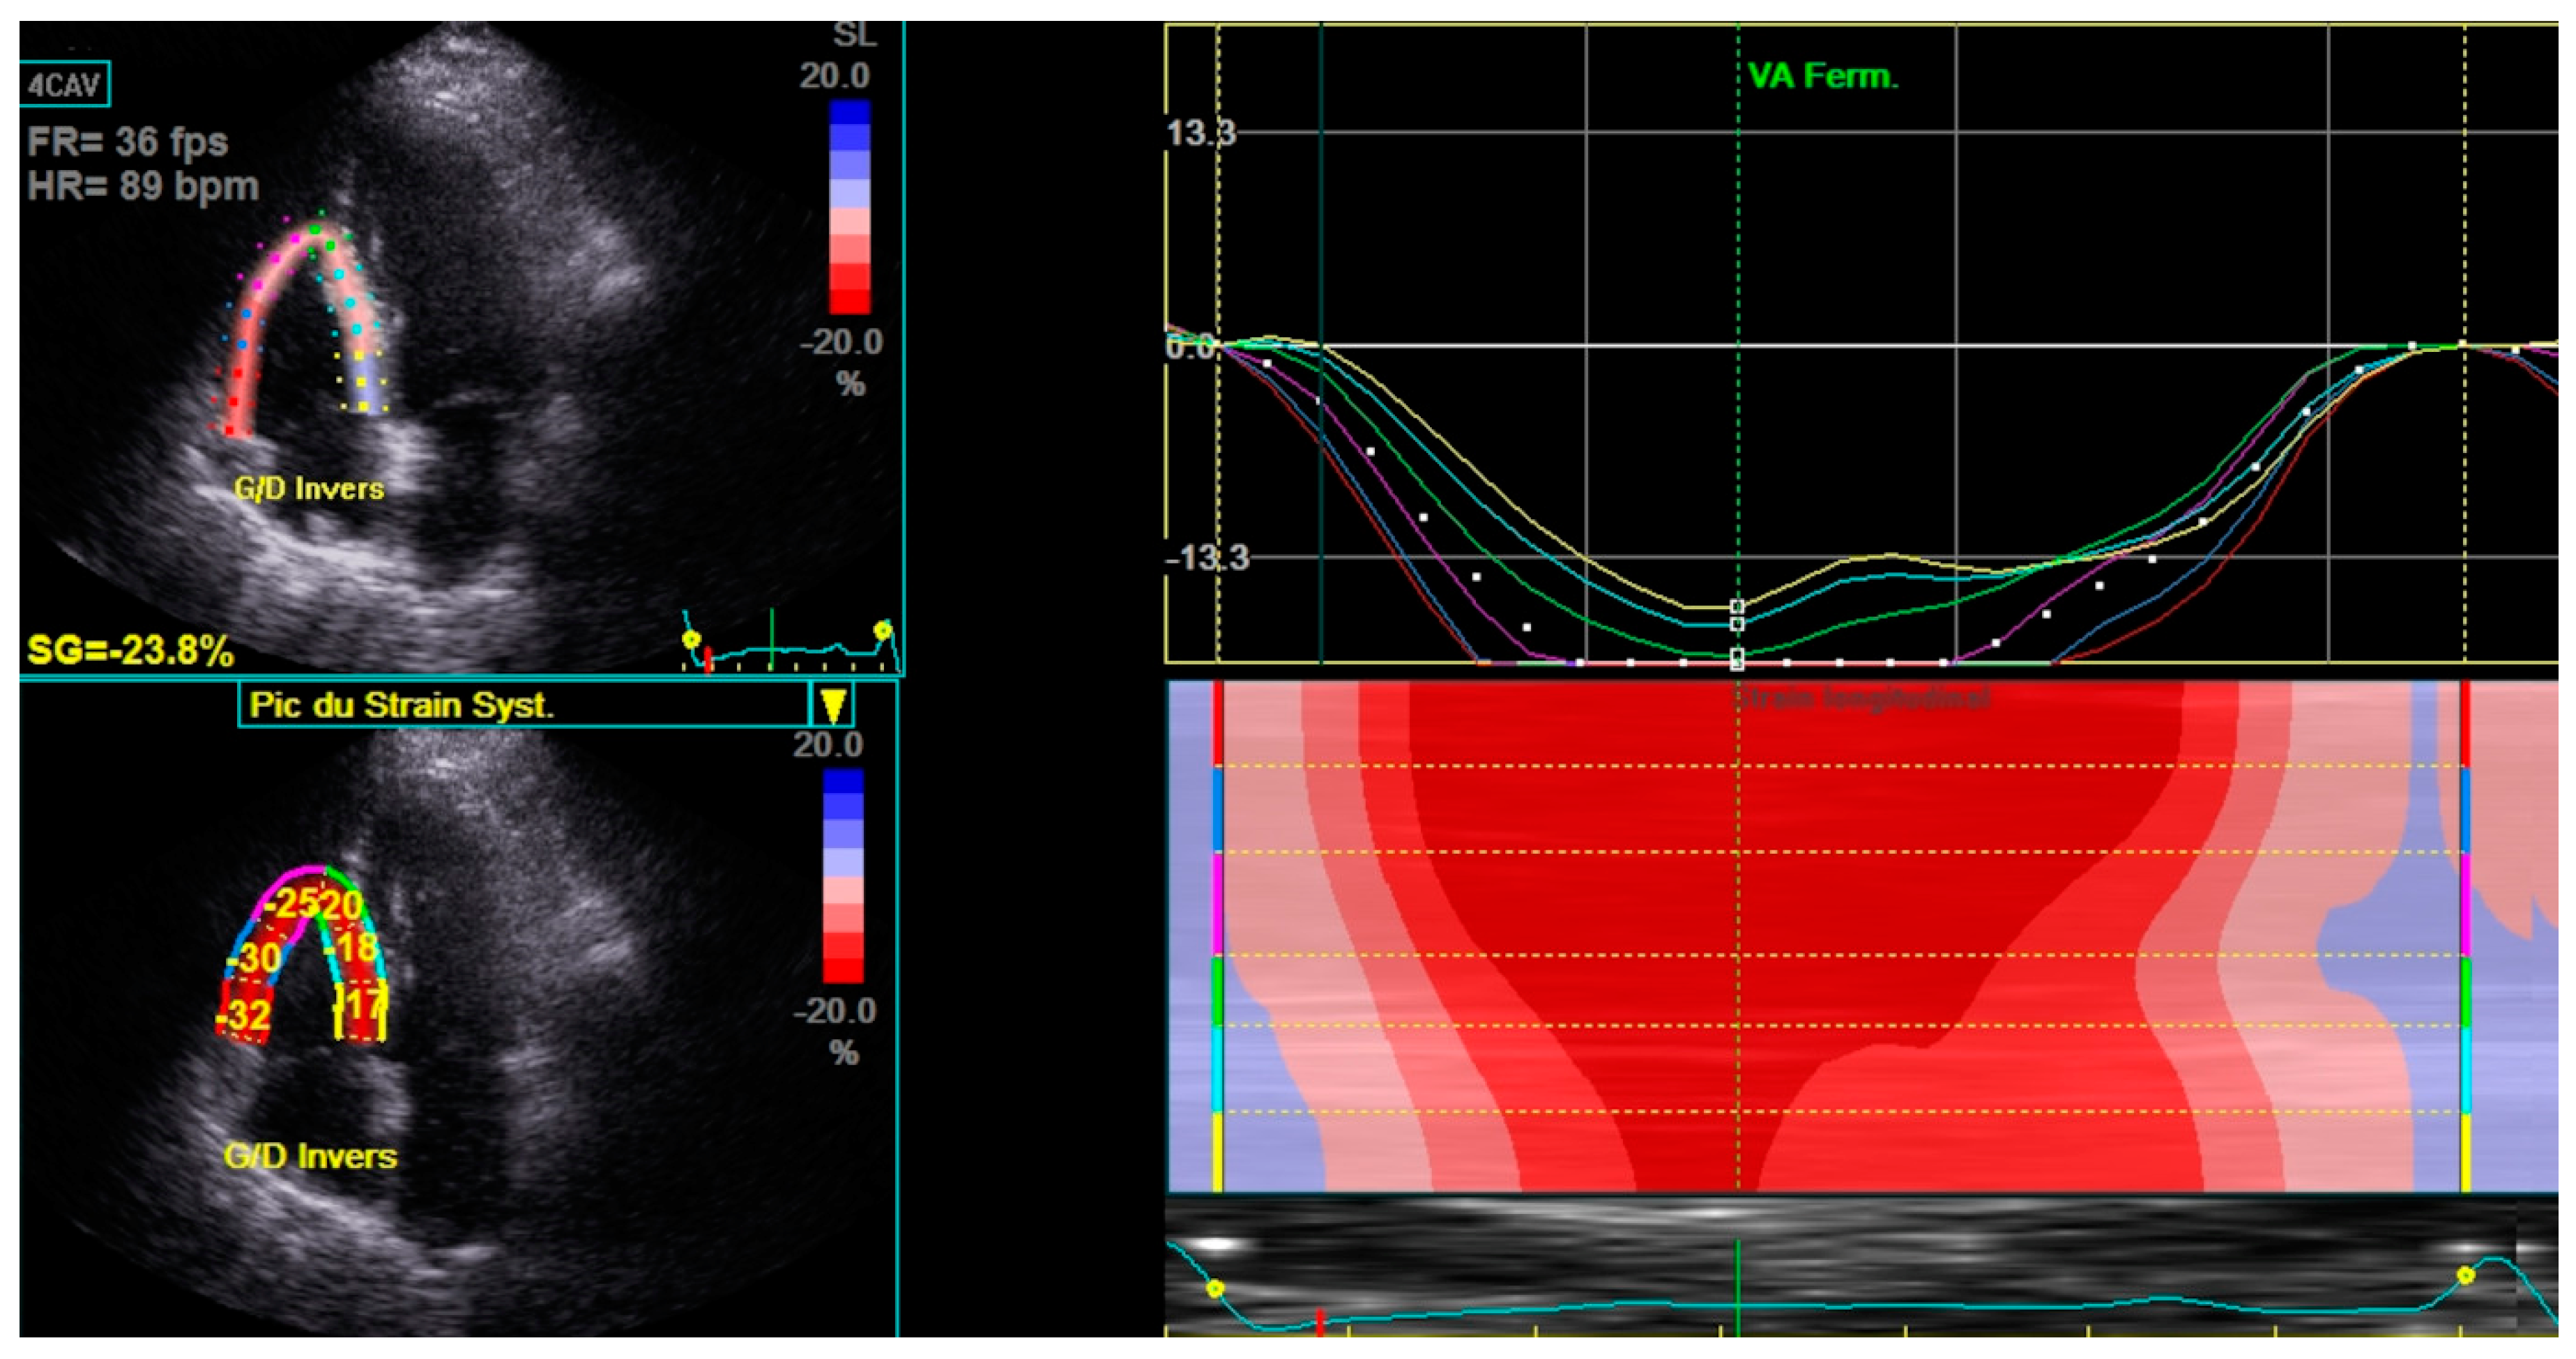

| RV Strain (%) | -19.9±3.7 |

| LV GLS (%) | -21.1±2.4 |